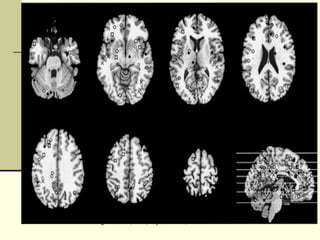

Brain activations of “selfing” - Gillihan, et al., Psych Bulletin, 1/2005

Brain activations of“selfing” - Gillihan, et al., Psych Bulletin, 1/2005

(adapted from) M.T. Alkire et al., Science 322, 876-880 (2008) Key Brain Areas for Consciousness